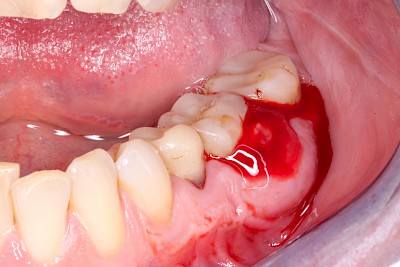

Schwellung mit Eiter: Abszess

Schwellungen im Zusammenhang mit akuten Entzündungen im Bereich der Zähne oder dem Zahnhalteapparat entstehen meist aufgrund schneller und starker Vermehrung von Bakterien sowie einer starken Abwehrreaktion des Körpers (Abszess). Diese Schwellungen entstehen meist in sehr kurzer Zeit – innerhalb von Stunden oder wenigen Tagen. Die Schwellungen sind sehr schmerzhaft. Nah am Zahnfleisch kann sich bei leichtem Druck auf die Schwellung Eiter entleeren. Mitunter fühlen sich die Menschen krank. In fortgeschrittenem Stadium kann auch Fieber auftreten. Hier ist sofort der Zahnarzt zu kontaktieren, um eine weitere Ausbreitung der Entzündung zu verhindern.

Einschmelzung & Geschwür

Das Risiko für Krebs der Mundhöhlen-Schleimhäute ist bei Menschen, die jahrelang übermäßig viel (Abusus) geraucht und erst recht lange übermäßig viel Alkohol getrunken haben, stark erhöht. Die Schleimhäute sehen dann aus wie "wildes Fleisch" – entweder mit blumenkohlartigen Auftreibungen oder aber es zeigen sich großflächige ungleichmäßig geformte Defekte und Einschmelzungen. Man spricht dann auch von einem Geschwür (Ulcus).